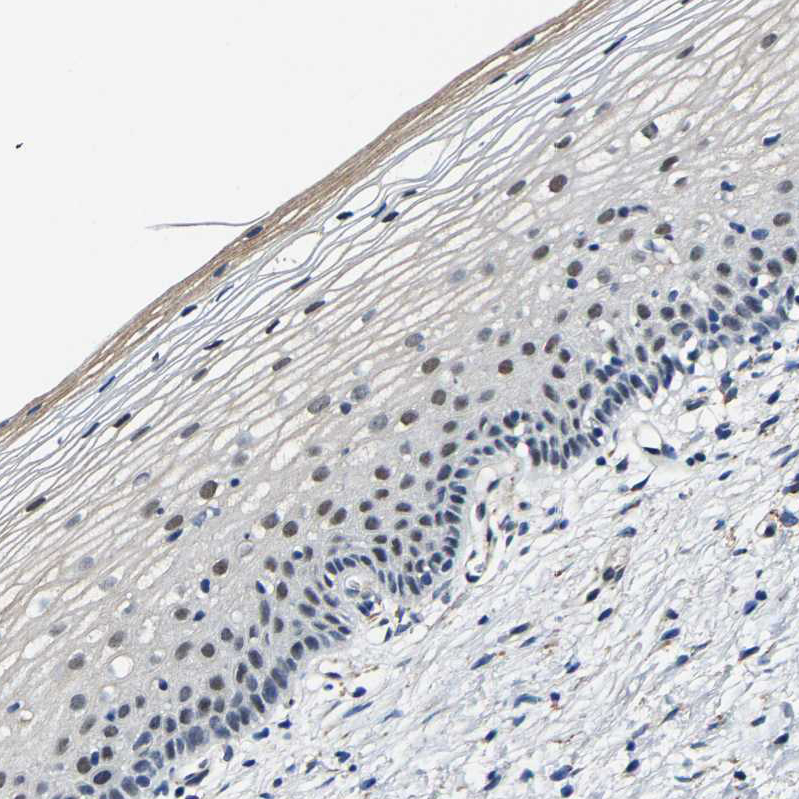

Immunohistochemical staining of human urinary bladder shows strong nuclear positivity in urothelial cells.